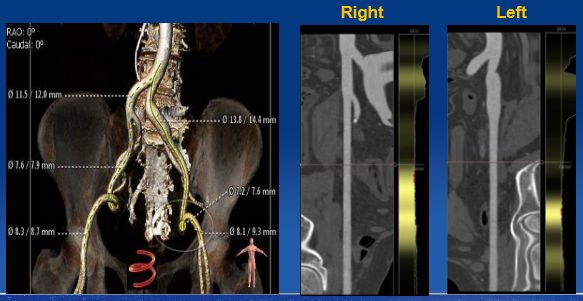

通过对CT图像的三维重建及分析可以提供左心室流出道、主动脉瓣环、主动脉窦部、窦管交界及升主动脉多平面的尺寸(包括长径、短径、周长和面积),冠状动脉开口的高度及其与临近解剖结构的关系,及主动脉根部的钙化情况,指导人工瓣膜尺寸的选择、TAVR手术规划。同时CT扫描可以评估外周血管的内径、扭曲度、钙化等情况,指导手术入路的选择。通过准确的测量我们可以充分评估患者是否适合TAVR手术,并且人工瓣膜的尺寸选择及手术规划。MDCT评估结果见Figure 4~Figure 7。

Figure 4

CT评估主动脉瓣环及主动脉窦部

Figure 5

CT评估钙化形态及分布

Figure 6

CT评估冠脉开口高度及瓣环角度

Figure 7

CT评估股动脉入路